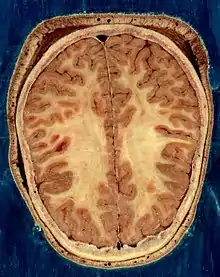

The vertebrate nervous system can also be divided into areas called gray matter and white matter.[18] Gray matter (which is only gray in preserved tissue, and is better described as pink or light brown in living tissue) contains a high proportion of cell bodies of neurons. White matter is composed mainly of myelinated axons, and takes its color from the myelin. White matter includes all of the nerves, and much of the interior of the brain and spinal cord. Gray matter is found in clusters of neurons in the brain and spinal cord, and in cortical layers that line their surfaces. There is an anatomical convention that a cluster of neurons in the brain or spinal cord is called a nucleus, whereas a cluster of neurons in the periphery is called a ganglion.[19] There are, however, a few exceptions to this rule, notably including the part of the forebrain called the basal ganglia.[20]